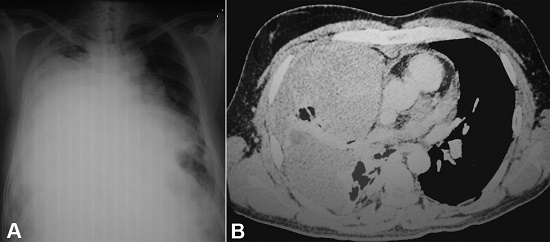

A 42-year-old previously healthy male was referred to our tertiary center complaining of high-grade fever accompanied by chills over the last 20 days. He also complained of progressively increasing breathlessness, nonproductive cough, and right-sided chest pain. There was no history of weight loss or abdominal pain. He denied smoking tobacco. On arrival at our center, he was found to be febrile and dyspneic. His pulse was 120/min, respiratory rate 28/min, and SP02 was 95% at room air. The systemic examination of the chest revealed decreased breath sounds in the right lower zone and coarse crackles in the right infrascapular region. No peripheral or deep chain lymphadenopathy was detected on physical or imaging examinations. The hematological workup showed a leukocyte count of 18,000/µl (reference range [RR]; 4000-12000/μL) with 80% polymorphs. Liver and renal function tests were within normal limits. The serum lactate dehydrogenase (LDH) was 1650 U/L (RR; 150-250U/L). The chest X-ray revealed a heterogeneous opacity in the right pulmonary lower lobe and pleural effusion, which showed to be hemorrhagic after diagnostic thoracocentesis (Figure 1A). The computed tomographic (CT)-guided Tru-cut biopsy attempted in the original-attending hospital showed necrotic tissue. The thoracic CT scan after the second hospitalization revealed a well-defined irregularly, marginated, complex, non-enhancing mass in the right lung, likely pleural based with thickened visceral pleura causing collapse and consolidation of the right lung (Figure 1B). The radiological differentials comprised malignant mesothelioma versus a synovial sarcoma.